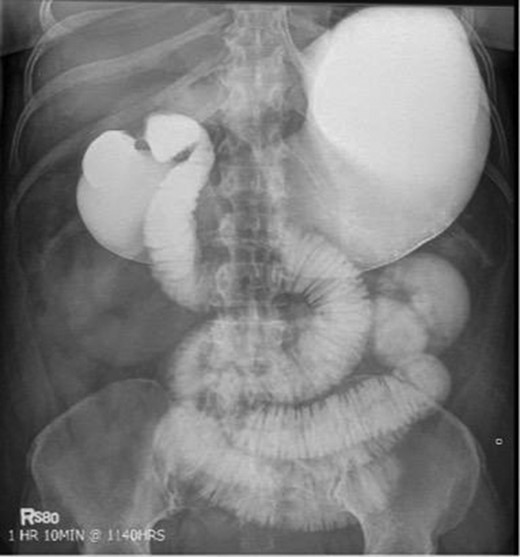

Laboratory studies were remarkable for leukocytosis, and an elevated lactate that improved with hydration (Fig. 1), while urinalysis was unremarkable. Abdominal CT scan obtained at this time demonstrated a partial SBO in the mid-small bowel as well as inflammation and thickening of the duodenum. A small bowel series was ordered, and showed high grade SBO (Figs 2–5).

Fluoroscopic barium study demonstrating oral contrast agent progression through the small bowel at 5 h after ingestion. Dilated bowel loops can be visualized throughout the abdomen, and transit time is delayed. Impression—high-grade distal small bowel obstruction.